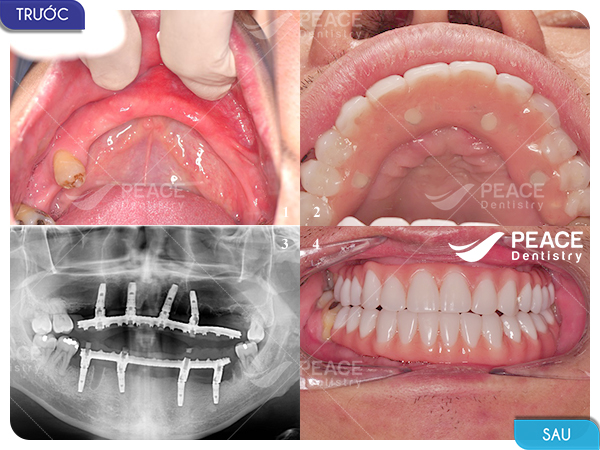

Hình ảnh thực tế